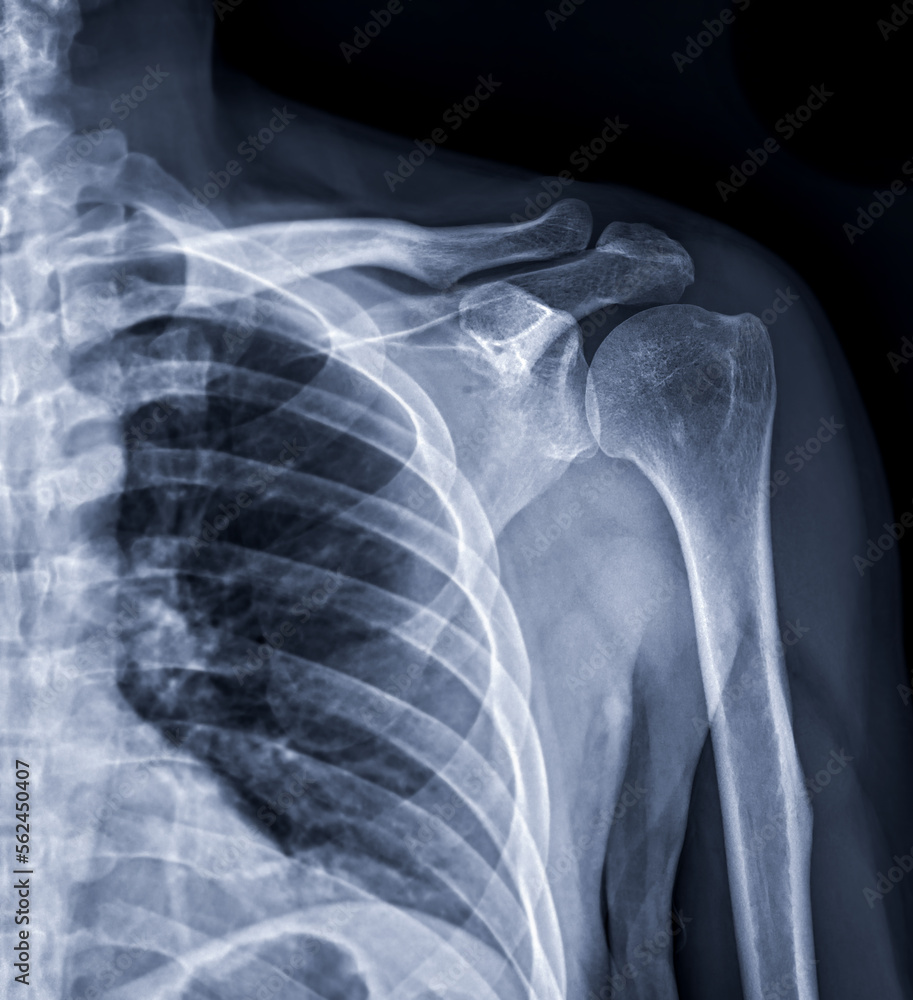

X Ray Of Shoulder Joint With Arthritis . Glenohumeral arthritis, or shoulder arthritis, is a degenerative joint disease of the shoulder characterized by damage to the. Shoulder arthritis occurs when the cartilage starts wearing down on the ball and/or socket sides of the shoulder joint. Shoulder radiographs are often the only imaging exam necessary for the evaluation of acute shoulder trauma, calcific tendonitis,. Symptoms of shoulder arthritis may include pain in the shoulder joint,. They can’t directly show cartilage, but your provider can see the amount. Pain when pressure is placed on the joint;